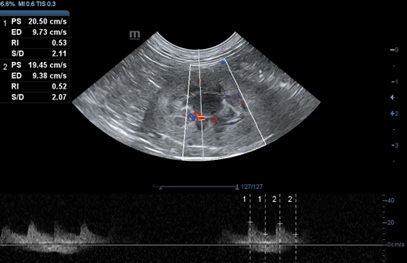

신장에서의 저항지수(RI)는 혈관 저항을 추정하기 위해 사용되며, 신장의 혈관(주로 엽간동맥(interlobar artery) 또는 궁상동맥(arcuate artery)의 펄스파 도플러를 이용하여 측정합니다. 계산은 최대 수축기의 혈류속도(Peak systolic velocity)에서 이완기말 혈류속도(End diastolic velocity)를 뺀 뒤, 이를 최대 수축기의 혈류속도로 나눈 값으로 산출됩니다(그림 4).

여기서 RI의 값이 0.7 혹은 0.71 이상을 보이면 비정상으로 생각되어 집니다. RI 값이 정상 범위에 속한다 할지라도, 같은 환자의 두 신장에서 차이가 0.10 이상이 되면 편측성 신장에 문제가 있음을 아는 데 도움이 됩니다.

박 등4) 은 고양이의 RI 측정에서 좌신에서는 0.52±0.05, 우신에서는 0.55±0.05로 보고하였으며, 신장의 크기와 RI는 체중과 통계학적으로 관련성이 있음을 밝혔습니다. RI의 증가는 비특이적 소견이며, 급성 폐색, 급성 신질환, 급성 세뇨관 괴사, 사구체질환, 신장 주변 혹은 피질하 액체 저류나 심한 저혈압에서도 나타납니다. 따라서 RI 평가는 신장 질환의 존재를 알아내는 것보다는 보조적인 진단도구로 사용해야 합니다.